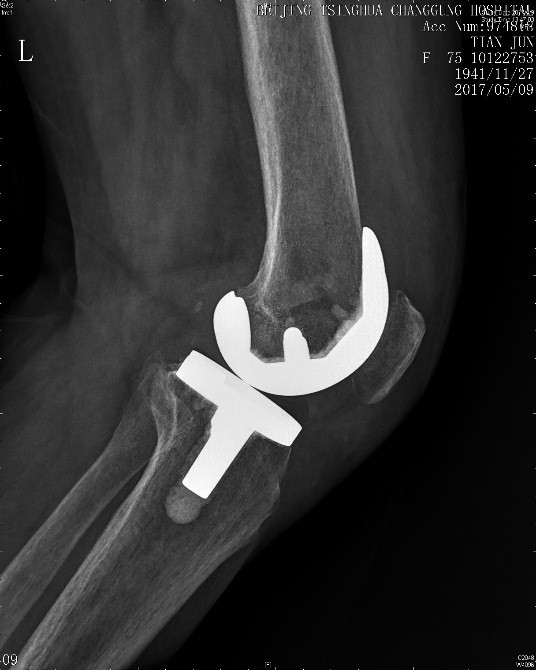

田阿姨今年75岁,左膝关节肿胀,疼痛,活动受限有5年多了,因为膝关节的问题去过许多大医院,专家都建议她做膝关节置换手术治疗,今年终于下定决心,在某专科医院做了左膝关节置换手术。手术做完2个月,田阿姨的膝关节仍然疼痛明显,下不了地,家属推轮椅来到了医院就诊。仔细查体可见左膝关节前可见手术伤口,愈合良好,无红肿渗出。左膝关节肿胀,伤口周围压痛明显,左膝关节屈伸活动明显受限,屈伸活动时伴疼痛,膝关节活动度为10-80度,左下肢髂腰肌肌力减弱。

图1 膝关节置换术后左膝关节X线检查